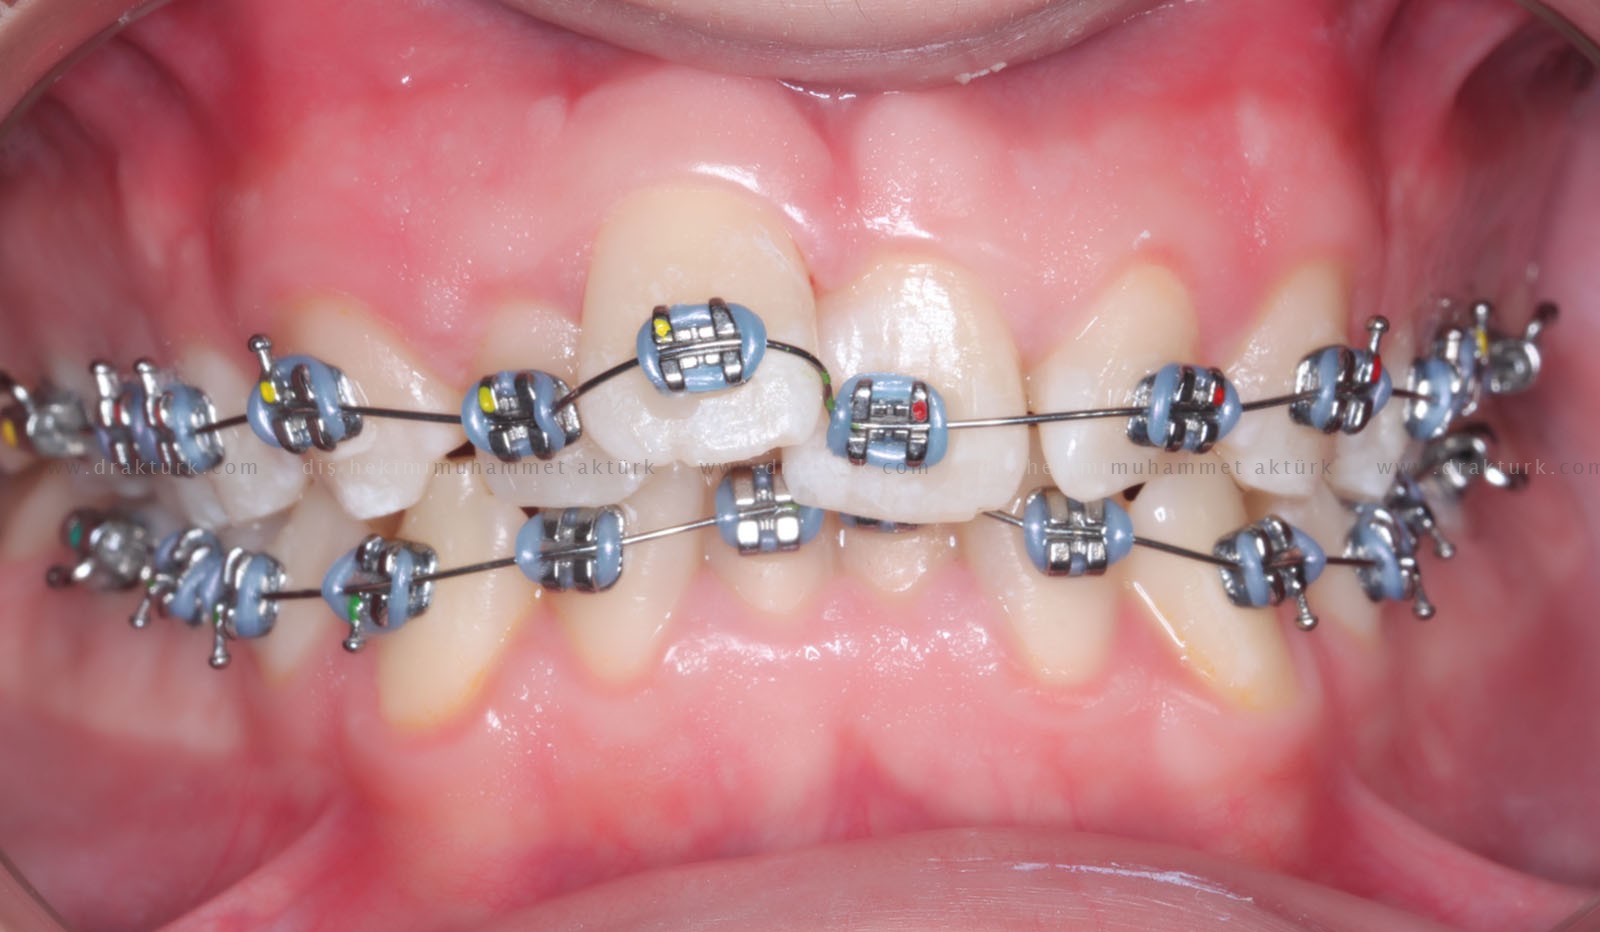

An example of the treatments we have done :

EXAMPLE ORTHODONTIC TREATMENT IN OUR CLINIC

Before

Before

Before

Before

Before

Before

After

After

After

After

After

After

Klinik Trabzon Oral and Dental Health Clinic, located in Trabzon, Turkey, provides comprehensive dental services across all specialties with our experienced physician staff. We specialize in advanced treatments including dental implants, cosmetic dentistry, porcelain veneers, zirconia crowns, orthodontics (including Invisalign), and pediatric dentistry.